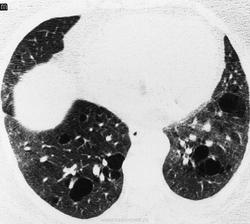

Дженнифер П. Mayberry, Стивен Л. Примак, Нестор Л. Мюллер

Сиалограмма левой околоушной железы - Sjogrens синдром

Шегрена синдром

http://www.ajronline.org/doi/full/10.2214/ajr.175.3.1750829